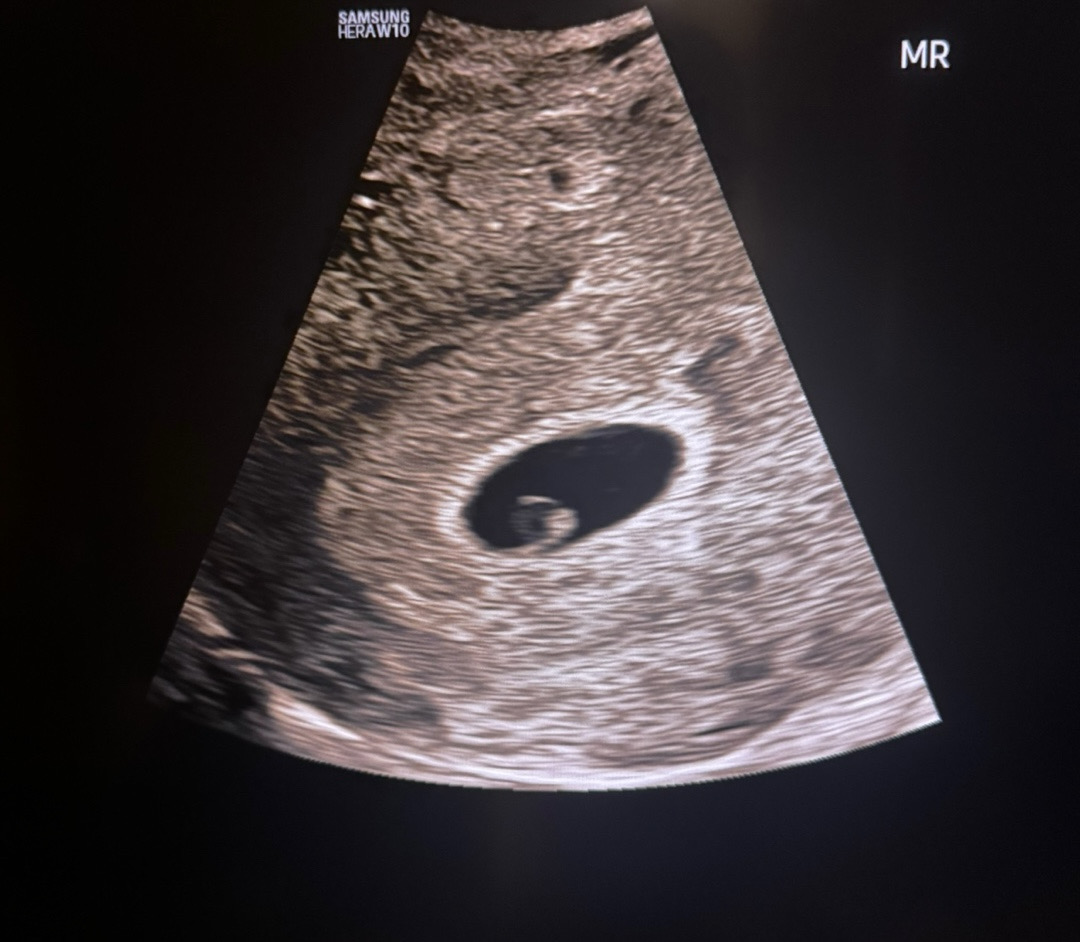

5주5일 아기집 난황 보고왔어용!

심장 소리는 못듣구, 콩닥콩닥 뛰는거만 봤네용 ! 다음주 월요일에가서 심소 들을거같아요 😵💫

난황이 크게 잘보여서 심장소리도 잘들으실게에요! 건강만챙기세요